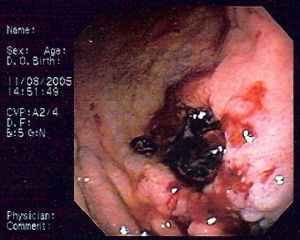

胃黏膜相關淋巴組織淋巴瘤1、非霍奇金淋巴瘤﹝Non-HodgkinLymphoma﹞有兩種類型: